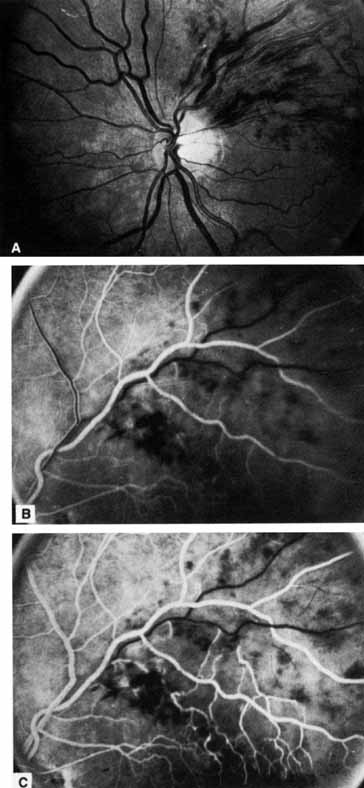

HEMICENTRAL AND HEMISPHERIC RETINAL VEIN OCCLUSION

The terms hemicentral, hemiretinal, and hemispheric retinal vein occlusion refer to eyes in which approximately half the venous outflow from the retina, either the superior or the inferior, has been occluded. In approximately 20% of eyes, the branch retinal veins draining the superior and inferior halves of the retina enter the lamina cribrosa separately before joining to form a single central retinal vein.175 Hemicentral retinal vein occlusion is an occlusion of one of these dual trunks of the central retinal vein within the nerve.176,177 Hemispheric retinal vein occlusion is an occlusion involving the venous drainage from approximately half of the retina, either the superior or the inferior retina (Fig. 7; see Fig. 11).75,178 This has also been referred to as a hemiretinal occlusion.362,363 In some eyes, the occlusion occurs in one of the dual trunks of the central retinal vein in which such a pattern exists (and then would qualify as a hemicentral retinal vein occlusion); the term hemispheric retinal vein occlusion actually includes the term hemicentral retinal vein occlusion.

Fig. 7 Equator-plus (A) and 30° photograph (B) of a hemispheric branch retinal vein occlusion.

In some eyes, the nasal retina is not drained by a separate vein, but by a branch of either the superior or the inferior temporal vein.179 It is the occlusion of one of these veins draining both the nasal retina and the superior or inferior retina near the optic disc that accounts for the majority of hemispheric retinal vein occlusions.75 In some eyes, however, it is impossible to determine the site of occlusion even with a good-quality fluorescein angiogram,75 and that is why we prefer the term hemispheric to describe this type of occlusion. The retinal area involved, appearance, clinical course, and complications from neovascularization are similar for both entities (see Table 2). The treatment and classification are similar to that of branch retinal vein occlusion.

The Eye Disease Case-Control Study reported the risk factors for a hemispheric or hemiretinal vein occlusion in a prospective study at five eye care centers.362 The three factors that were significantly associated with this type of occlusion compared to control were systemic hypertension, diabetes mellitus, and glaucoma. A reduction in risk with moderate alcohol consumption was noted, but it was not statistically significant, possibly because of the small number of cases (79) in this series.362 The study felt that there were more similarities than dissimilarities in the risk factor profiles for central retinal vein occlusion, branch retinal vein occlusion, and hemispheric or hemiretinal vein occlusion.362,363

We have seen one patient in whom a superotemporal branch retinal vein occlusion developed in the same eye with an inferior hemispheric retinal vein occlusion, producing the appearance of a three-quarter retinal vein occlusion.

Back to Top

BRANCH RETINAL VEIN OCCLUSION

Branch retinal vein occlusion involves one of the branch retinal veins and generally is less visually disabling than either a central or hemispheric retinal vein occlusion. The occlusion may involve either a small, localized area of the retina or as much as an entire quadrant (Fig. 8).179,180 Its incidence in an outpatient referral setting is roughly the same as that of central retinal vein occlusion.181 The occlusion of a macular vein is a distinct entity that is discussed separately.182

Fig. 8 A. Nonischemic superior temporal branch retinal vein occlusion. The visual acuity is reduced because of mild macular edema. B and C. The intravenous fluorescein angiogram shows the nonischemic nature of this occlusion and macular edema in the late stage of the angiogram.

Most branch retinal vein occlusions involve veins located temporal to the optic disc; it is rare for a branch retinal vein occlusion to occur in the nasal retina. Whether this is because the incidence is truly rare or because these occlusions are generally asymptomatic and discovered only incidentally is unknown. There are significantly more vein-posterior than vein-anterior crossings in the superotemporal than the inferotemporal quadrant, and vein-posterior crossings are more likely to be obstructed than vein-anterior crossings.413 Occasionally a branch retinal vein occlusion occurs nasally and involves the entire nasal retina.

PATHOLOGY

Leber183 was probably the first investigator to note the connection between branch retinal vein occlusion and the arteriovenous intersection. Koyanagi184 found that the majority (77.7%) of his cases of temporal vein occlusion involved the superior retina. He attributed this to the preponderance of arteriovenous crossings in this region compared with other quadrants.184 Others later confirmed this anatomic observation, noting that branch retinal vein occlusion always occurs at an arteriovenous intersection.184,185 Both fluorescein186,187,367 and indocyanine green392,393 angiography and histopathologic examination confirm that most occlusions occur at an arteriovenous crossing and that the few that do not are in the vicinity of a retinal artery.188 Histologically, where the vein and artery cross, they share a common adventitial sheath, and the venous lumen may be diminished by as much as a third at this crossing.189,190

An anterior location of the artery (vein-posterior crossing) in relation to the vein at the arteriovenous crossing is an important risk factor for a branch retinal vein occlusion. The artery is located anterior to the vein (toward the vitreous) in more arteriovenous crossings where a branch retinal vein occlusion exists than in unobstructed arteriovenous crossings,191–195 although the risk seems to apply only to second-order arteriovenous crossings.196

Frangieh and co-workers188 histopathologically studied nine eyes with branch retinal vein occlusion and hypothesized that the primary event was a thrombosis of the venous system, followed by secondary capillary and arterial changes, and eventually by neovascularization.

A series of experiments on monkeys has shown what happens histopathologically after a branch retinal vein occlusion.19–21 The occlusion is divided into three stages:

First stage (1 to 6 hours after occlusion): As a result of outflow occlusion, there is a rise in the intravascular pressure with capillary leakage and retinal edema and probably leakage from endothelial junctions that have been temporarily disturbed.

Second stage (6 hours to 1 week after occlusion): This stage is characterized by flattening of some of the vessels, followed by degenerative changes in the endothelium and pericytes. Necrosis of the endothelium results in exposure of the basement membrane, and platelet thrombi form. This capillary degeneration is associated with complete microvascular stasis. Retinal hemorrhage appears at this time.

Third stage (1 to 5 weeks after occlusion): At this stage, empty basement membranes are left, and capillary closure is irreversible because proliferating glial cells have entered the ghost vessels. This sequence of events has been termed ischemic capillaropathy.22

The experimental work of Hamilton and associates19 demonstrates that progressive capillary nonperfusion can result from isolated outflow occlusion and does not require an arterial occlusion. Other investigators have been able to reproduce the clinical appearance of branch retinal vein occlusion, including neovascularization, in animal models.197–201,368–370

ETIOLOGY

Branch retinal vein occlusion is caused by an obstruction of one of the branch retinal veins in the retina. The largest study to address the risk factors associated with branch retinal vein occlusion was undertaken by the Eye Disease Case-Control Study Group; they studied 270 patients with branch retinal vein occlusion compared with 1,142 control patients with standardized ocular, systemic, and laboratory examinations.202 They found that an increased risk of branch retinal vein occlusion in persons with a history of the following: systemic hypertension, cardiovascular disease, increased body mass index at 20 years of age, glaucoma, and higher serum levels of a2-globulin (Table 3).202 Almost 50% of the causes of branch retinal vein occlusion are associated with hypertension.202 Although diabetes mellitus is more common in patients with branch retinal vein occlusion than in controls, it is not a strong independent risk factor for branch retinal vein occlusion.202 It is not known whether serum levels of a2-globulin are a true marker for persons at increased risk, are a chance finding, or are a response to the occlusion itself.202

TABLE 3. Risk Factors for Branch Retinal Vein Occlusion

Increased RiskDecreased Risk

Systemic hypertension History of cardiovascular diseaseHigher levels of alcohol consumption

Increased body mass index at 20 years of ageHigher serum levels of-density Lipoprotein cholesterol